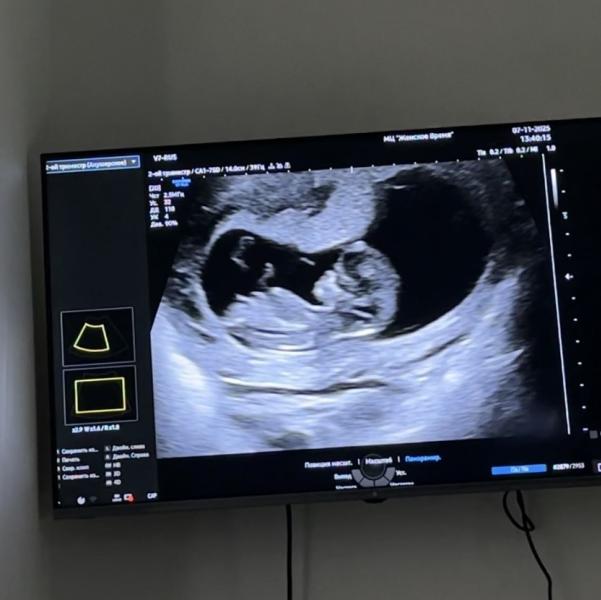

Определение пола ребенка на УЗИ: ждем результаты анализа

Моя булочка, врач предположила мальчика🙈Ждем кровь)

А по мне девчонка) у меня у мальчиков там торчало вверх, а тут направление вниз, ну может конечно в живую врачу было виднее, в любом случае, главное чтоб ребёнок был здоров🥰

Да🥰 Ну я почему-то тоже сомневаюсь и думаю девченка)